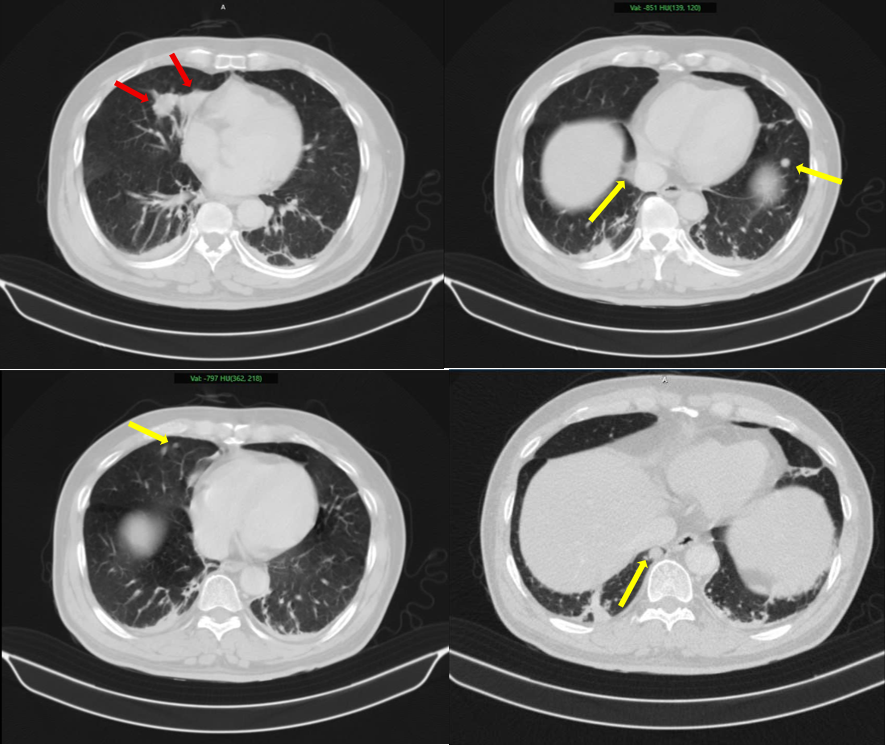

Cảnh báo ungthư phổi gia tăng: Bác sĩ khuyên tránh 4 loại thực phẩm để lâu trong tủ lạnh

( PHUNUTODAY ) – Gần đây, số ca mắc bệnh về phổi có xu hướng gia tăng, đáng chú ý là không chỉ người hút thuốc mà cả người không hút thuốc cũng được chẩn đoán mắc bệnh, khiến xu hướng này trở nên đáng lo ngại. Phản ứng đầu tiên của nhiều người khi […]